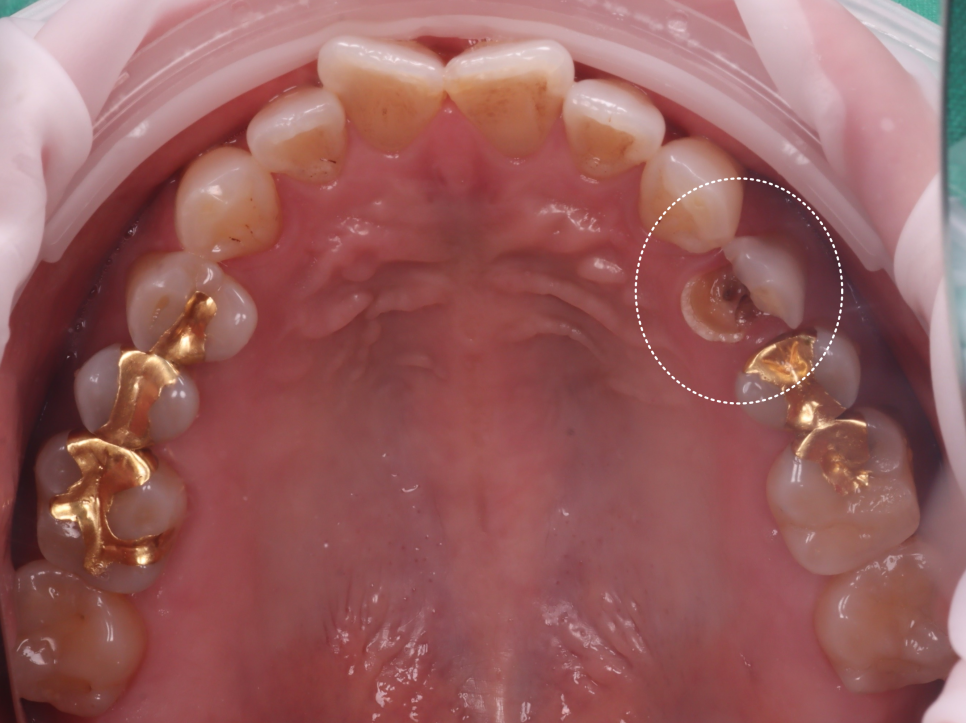

촬영일 : 250901

파노라마와 구내 사진, 탐침 검사로 확인하니

손상이 생각보다 컸고

충치가 깊이 진행되었어요.

내용물을 정리해 보니 신경(치수)이

이미 오염되어 있었어요.

신경치료(근관치료)가 먼저였죠..